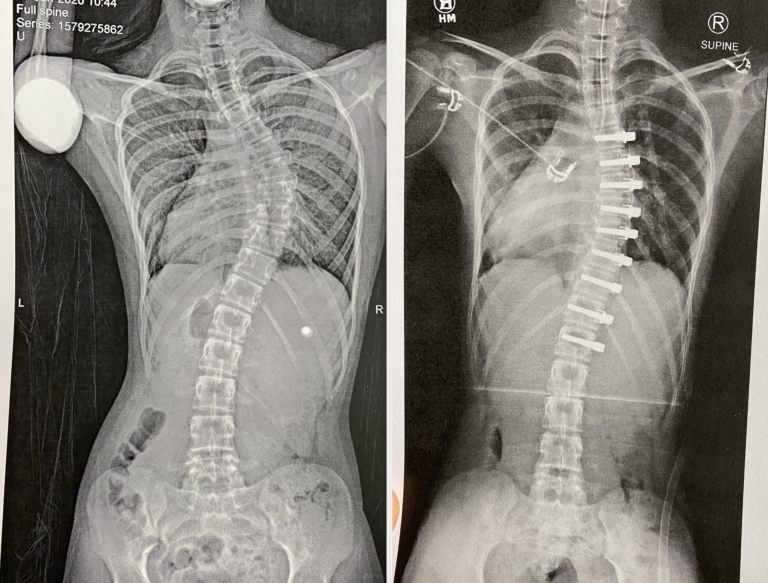

Idiopathic EarlyOnset Scoliosis Treated With Magec Rods What to Do

Idiopathic EarlyOnset Scoliosis Treated With Magec Rods What to Do Flexible Rods For Back Surgery polyetheretherketone (peek) rods for lumbar fusion have been available since 2007. in this article, three rod concepts—the rigid rod, semirigid rod, and memory rod—described in the previously published literature have been reviewed. peek rods provide a secured flexible stabilisation with a low rate of both reoperations and serious complications. rods that are secured to the pedicle. Flexible Rods For Back Surgery.

Idiopathic EarlyOnset Scoliosis Treated With Magec Rods What to Do Flexible Rods For Back Surgery When these rigid rods are connected to. in this article, three rod concepts—the rigid rod, semirigid rod, and memory rod—described in the previously published literature have been reviewed. polyetheretherketone (peek) rods for lumbar fusion have been available since 2007. The flexible portion of the rod. rods that are secured to the pedicle screws are typically rigid and. Flexible Rods For Back Surgery.

Before and After Scoliosis Surgery with Darryl Antonacci Flexible Rods For Back Surgery polyetheretherketone (peek) rods for lumbar fusion have been available since 2007. dynamic stabilization uses rods made of flexible materials to stabilize the affected level of the spine. The flexible portion of the rod. peek rods provide a secured flexible stabilisation with a low rate of both reoperations and serious complications. in this article, three rod concepts—the. Flexible Rods For Back Surgery.